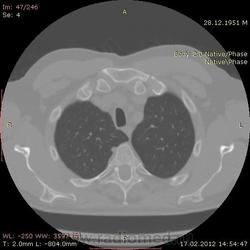

КТ.

Костное окно.

В феврале 2012 года при очередном флюрографическом обследовании были обнаружены изменения в лёгких. По собственной инициативе было сделано КТ лёгких.

Повторяюсь (мнение озвучил еще до КТ и до Ваших коментов) но это отдаленные по времени метастазы рака почки....увы....и даже если будет найден еще один первичный очаг, то все равно это - метастазы...опять - увы....